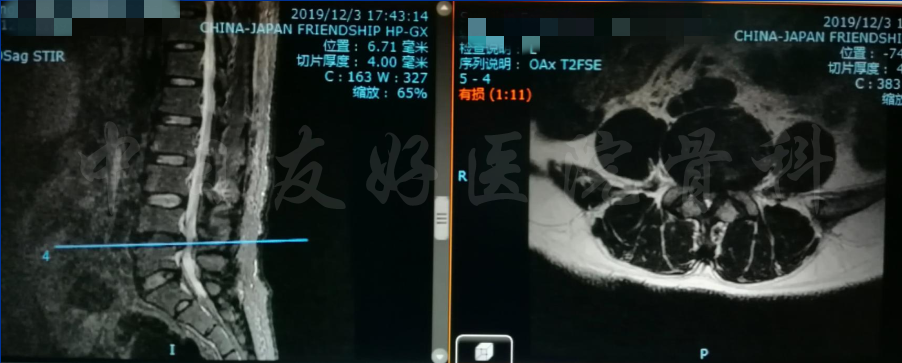

MRI

MRI

MRI

矢状位MRI

轴位MRI:腰3-4(左)、腰4-5(中)、腰5骶1(右)

腰椎MRI